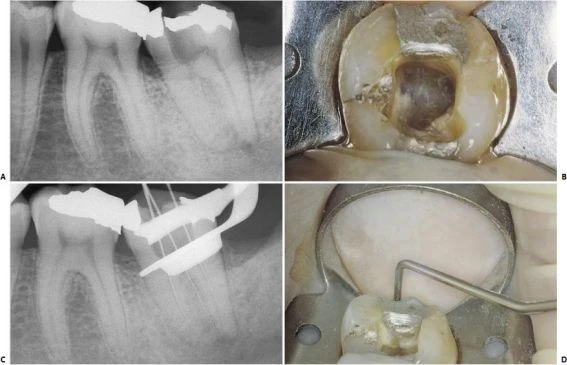

–  Trong 35% trường hợp có sự hiện diện của 4 ống tủy. Chân xa có 2 ống tủy, 1 ở phía ngoài và 1 ở phía trong (hình 11.109).

Hình 11.109. A. Phim sau điều trị của  RCL 1 dưới. B. Nhìn theo chiều gần xa trên cùng răng đó có thể thấy có 2 ống tủy ở chân xa, các ống tủy chân gần mặc dù gặp nhau ở 1/3 giữa nhưng vẫn có 2 lỗ chóp. C. Xoang tủy ở R36 với 2 ống tủy ở chân gần và 2 ống tủy ở chân xa. D.Trong trường hợp răng cối lớn dưới khác cũng có 4 ống tủy, mỗi ống tủy có 1 lỗ chóp riêng.